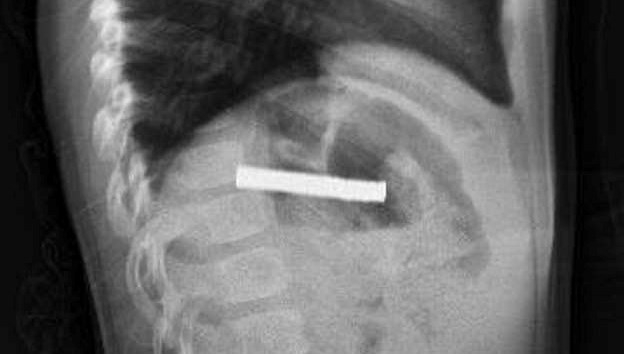

Boğazından 19 adet mıknatıs çıkartıldı

Elazığ’da 3 yaşındaki bir çocuğun yuttuğu 19 mıknatıs, Fırat Üniversitesi Hastanesi’nde başarılı bir operasyon ile çıkartıldı.